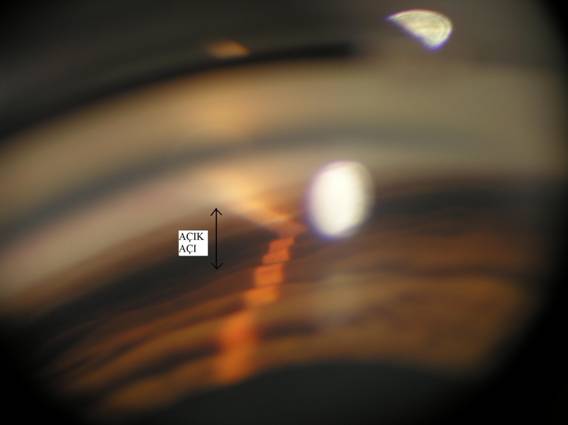

Erişkinlerde görülen glokom hastalığını “açık açılı” ve “dar açılı” olarak ikiye ayırmak mümkündür. Daha sık görülen (tüm glokomların yaklaşık dörtte üçü) “açık açılı” glokomda sıvının çıktığı kanal sistemi muayene edildiğinde normal (açık) olduğu saptanır, ancak mikroskobik düzeydeki bozukluklar sıvının gözü terk etmesini zorlaştırmakta ve sonuçta göz tansiyonu yükselmektedir. Nispeten seyrek görülen “dar açılı” glokom ise genellikle hipermetrop gözlerin hastalığıdır, nispeten küçük olan bu gözlerde göz içindeki sıkışıklıktan dolayı göz içindeki sıvının göz içinde serbestçe dolaşımı engellenmekte ve sıvının gözü terk ettiği kanallar tıkanmaktadır. Sonuçta sıvı kanallarının tamamen devre dışı kalmasına bağlı olarak göz tansiyonu çok aşırı yükselip (göz tansiyonu krizi) çok kısa süre içinde kalıcı görme kaybı oluşturabilmektedir. Bu tür gözlerde eğer tam olarak kriz yoksa açık açılı glokom hastalarında olduğu gibi hiçbir belirti olmayabilir, bazen göz çevresinde ağrı ya da bir ışık kaynağına bakıldığında renkli haleler görülmesi söz konusu olabilir. Arzu edilmeyen böyle bir durumun ortaya çıkmaması için kriz riski taşıyan gözlerin saptanması çok önemlidir. Bunun için sadece göz tansiyonu kontrolü yeterli olmayabilir, şüphelenilen durumlarda mutlaka deneyimli bir uzman tarafından kanal sistemi özel bir mercekle muayene edilerek (gonyoskopi) riskli bir durum olup olmadığının kesin olarak ortaya konması gerekir.